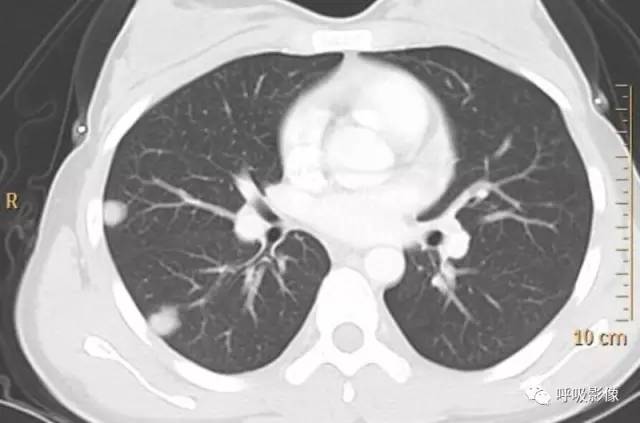

简单病史:女,35岁。查体发现肺部占位。胸部CT;右肺中叶外侧段近胸壁处圆形病变,边缘光滑,无毛刺, 增强扫描可见强化。

诊断: 肺良性肿瘤或孤立性转移瘤

诊断依据:青年女性,右肺中叶结节影,边缘光滑,密度均匀,无明显分叶、毛刺,临近胸膜无受累、肋骨无压迹,不符合肺恶性肿瘤诊断;患者无症状,不符合感染性疾病;病变密度均匀,内无坏死,无卫星灶,不符合结核球诊断。综合考虑肺良性肿瘤或孤立性转移瘤可能性大,病变位于胸膜下,孤立性转移瘤需考虑。病变增强扫描可见血管样强化,提示原发瘤血供丰富,最终病理为绒毛膜癌肺转移。